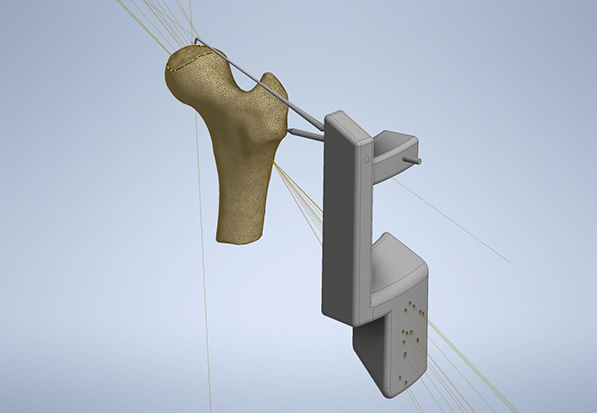

3D Model vodiča dizajniranog na

osnovu virtuelnog prikaza zgloba

pacijenta

Trodimenzionalno štampanje je generalno nova tehnologija koja omogućava da se prema digitalnom modelu nekog predmeta, nanošenjem tankih slojeva odabranog materijala, izradi realan trodimenzionalni predmet. Prema ovoj definiciji, 3D štampanje omogućava izradu i repliciranje bilo kog predmeta, pa tako i izradu personalizovanih hirurških instrumenata - PSI (Personalized Surgical Instruments), što je jedna od primena ove vrste tehnologije u ortopedskoj hirurgiji. Najćešće se izrađuju takozvani vodiči za uvođenje hirurških alatki u telo pacijenta, ili vodiči za sečenje kod nekih procedura (npr. kod ugradnje veštačkog kolena), koji se dizajniraju prema individualnim morfološkim karakteristikama kosti/zgloba acijenta.